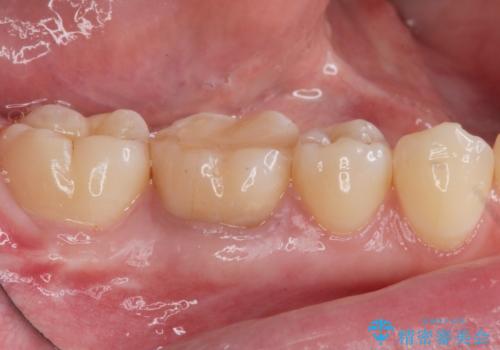

樹脂をセラミックにしたい ジルコニアクラウンでの治療

- 樹脂をやり替えたいとのことで来院されました。

特に大きな虫歯もありませんでしたが、残った歯が薄かったためクラウンでの修復処置を行いました。

- 右下6 仮歯+ジルコニアクラウン 11,000円+110,000円費用は治療当時の料金となります

インレーにすると残った歯が薄くなってしまう場合は術後の破折リスクが高いためクラウンで修復することがあります。